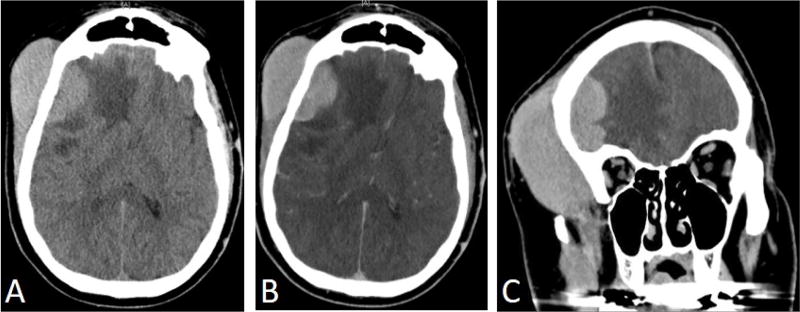

淋巴瘤表现为头皮肿块是一种罕见但严重的医学状况,需要积极治疗和神经外科干预。我们报告一个53岁的男性病例,他表现为右侧额部头皮肿块大,左侧额部头皮肿块小。在与患者讨论后,决定切除较大的肿块以确定诊断。肿块次全切除后,活检显示WHO 1级滤泡性淋巴瘤(FL),弥漫性IV期。患者随后接受了4格(Gy)的姑息性放疗,分2段对右侧额叶头皮进行放疗,并进行全身化疗免疫治疗(6个周期),随后进行了美罗华维持治疗。治疗开始一个月后进行腰椎穿刺取脑脊液,结果为恶性细胞扩散阴性。治疗开始约3个月后,PET/CT未显示活动性恶性肿瘤,MRI显示右侧额叶头皮肿物内部完全消退。我们用这个病例提供关于疾病病理生理,早期诊断和管理的详细讨论。

Lymphoma presenting as a scalp mass is a rare but serious medical condition mandating aggressive treatment and neurosurgical intervention. We report a case of 53-year-old male who presented with a large right sided frontal scalp mass and a smaller mass located on the left frontal scalp. After discussion with the patient, it was decided to resect the larger mass for definitive diagnosis. After subtotal resection of the mass, biopsy revealed WHO grade 1 follicular lymphoma (FL), diffuse pattern stage IV. The patient was subsequently treated with 4 grays (Gy) of palliative radiotherapy over 2 fractions to the right frontal scalp and systemic chemo-immunotherapy (6 cycles) followed by rituximab maintenance. Lumbar puncture to obtain cerebrospinal fluid was done a month after therapy began and the results were negative for spread of malignant cells. Approximately 3 months after initiation of therapy, PET/CT showed no evidence of active malignancy and MRI revealed a complete internal resolution of the enlarged right frontal scalp mass. We use this case to provide a detailed discussion regarding disease pathophysiology, early diagnosis, and management.